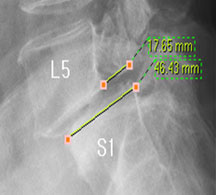

뼈가 앞으로 밀려나갔다고 하니 척추가 당장이라도 주저 앉을 것 같고, 한없이 밀려나갈 것 같지만 일반적으로 밀려나간 뼈는 대부분 1-2단계(25~50%) 정도 밀려나간 상태에서 안정화되는 경향을 보이기 때문에 그 자체로는 문제가 되지 않습니다.

즉, 척추전방위증은 통증을 일으키는 원인질환(디스크, 협착증)을 치료하는 것이 척추 뼈를 더 이상 앞으로 밀려나가지 않게 하는 치료라고 볼 수 있습니다. 모커리는 뼈가 50% 이상 밀려나간 2단계의 척추전방위증도 비수술로 치료하고 있으며, 이러한 한방치료 효과를 객관적으로 검증하여 유명학회 및 논문에 계속해서 발표하고 있습니다.

모커리한방병원은 2013년 1월부터 2014년 3월까지 척추전방위증으로 입원한 환자를 대상으로 치료 전•후를 비교분석한 결과, 복합척추치료 약 3주 후 환자가 느끼는 허리와 엉덩이 통증지수가 7.1에서 3.1로 줄었으며, 통증 없이 걸을 수 있는 거리 역시 193m에서 568m로 약 3배 가량 증가했습니다. 이번 연구결과를 계기로 50% 정도 밀려나간 2단계의 척추전방위증 환자들도 수술 없이 충분히 치료될 수 있다는 것이 객관적으로 검증되었습니다.

모커리한방병원은 50% 정도 밀려나간 2단계의 척추전방위증 환자를 대상으로 약 3주간의 입원집중치료를 실시한 결과, 입원 시보다 80% 이상 통증이 감소되어 치료되었습니다. 통증 없이 걷는 시간도 약 3배 정도 증가되어 단기간에 수술 없이 높은 치료효과가 나타났다는 것을 대한침구의학회에 발표하였습니다. 50% 정도 밀려나간 2단계의 중증 척추전방전위증 환자이면서 심한 척추협착증 증상을 나타내는 환자를 치료한 결과입니다.